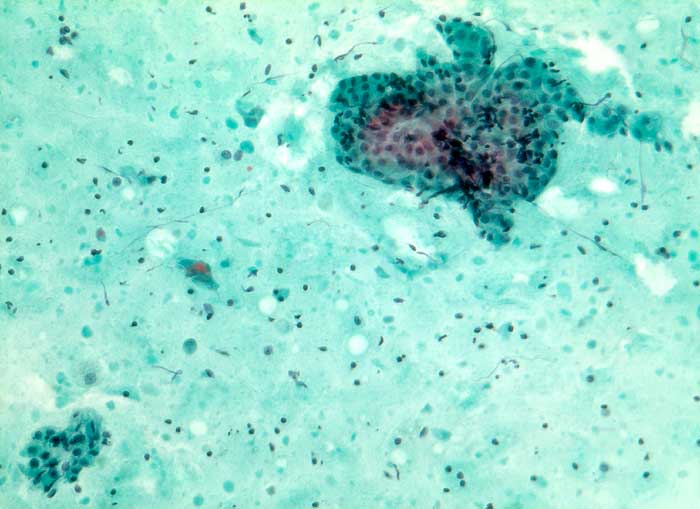

Warthin Tumor

benigner Tumor

Parotis

Feinnadelpunktion Parotis: Fein bis grobscholliger Detritus mit einzelnen schattenhaften Zellen und locker verstreuten Lymphozyten. Dazwischen hin und wieder Aggregate onkozytärer Zellen durchmischt mit vereinzelten Lymphozyten.

Unklare Schwellung Parotisunterpol

Zytologie

160